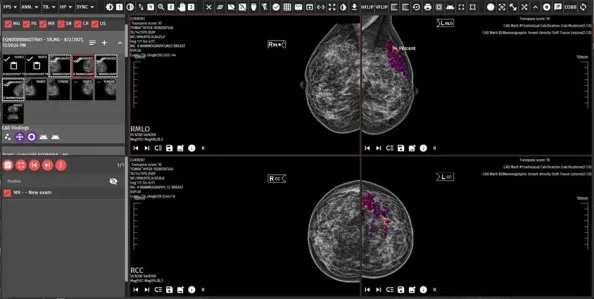

DevamıGelişmiş Görüntü İşleme Araçları

Farklı Segmentasyonlar ile Çalışabilen Görüntü İşleme Araçları